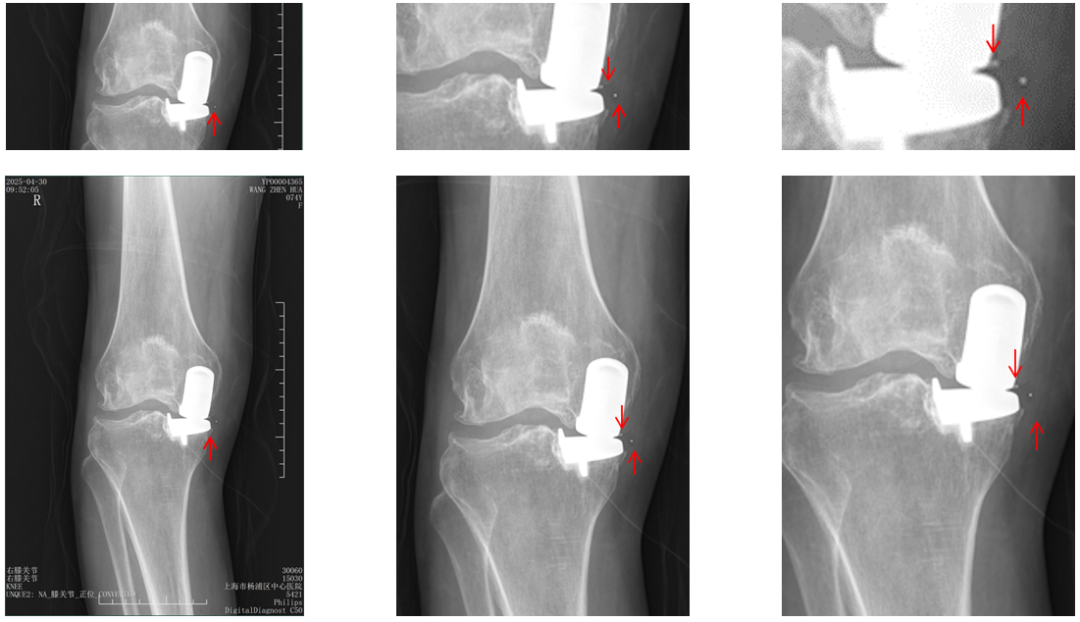

病例2:Bearing 破裂( X-ray正位)

解读:两个点都在内侧

病例2:Bearing 破裂( X-ray侧位)

解读:股骨假体与胫骨假体间隙还存在,在图像放大4倍情况下,才依稀看到模糊的点.

病例2:Bearing 破裂

病例2:Bearing 破裂的处理